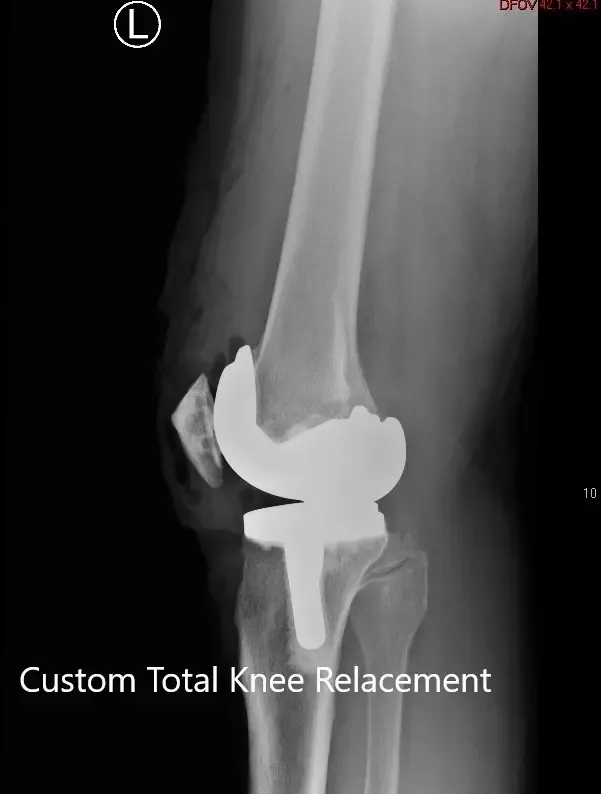

IMPLANTS USED: Custom femoral implant with a tibial tray with 6-mm polyethylene inserts on the right side with 29-mm patellar component. Custom femoral implant with a custom tibial tray with 6-mm polyethylene inserts on the left side with the 32-mm patellar implant.

Postoperative X-ray showing the lateral views of both knees.

Postoperative X-ray showing the AP view of both knees.